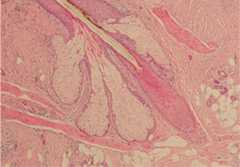

Cross section of a hair follicle:

The hair is composed of keratinized cells that emerge and migrate upward inside the hair follicle. When the hair shaft emerges from the skin surface, it does so at a slightly slanted angle. For every hair follicle, there is an adjacent sebaceous gland.